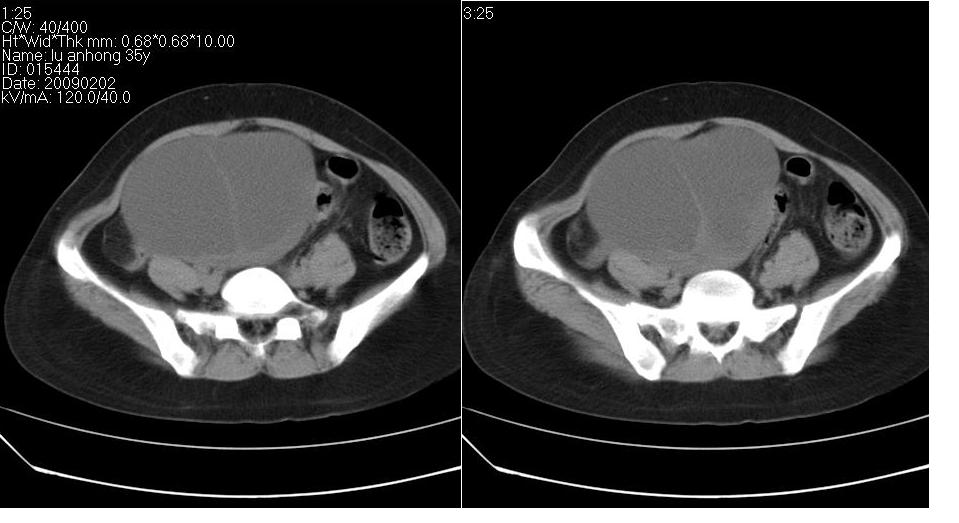

女 35岁,下腹部坠感疼,其它病史不详。图象顺序有点乱。

考虑右侧卵巢畸胎瘤。

定位于盆腔附件,有囊性密度,有脂肪密度、还有骨密度;应该是比较典型的卵巢畸胎瘤。